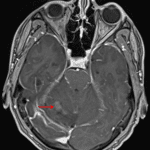

MRI

- Ill-defined T2/FLAIR hyperintense mass in the superior aspect of the right cerebellar hemisphere and superior aspect of the vermis measuring approximately 4.3 x 2.2 x 4.2 cm

- Nodular internal areas of restricted diffusion and corresponding patchy enhancement

- Peripheral susceptibility artifact about one of these nodular areas in the anterior aspect of the right cerebellar hemisphere, likely relating to hemorrhage

- Thickening and enhancement of the adjacent tentorial leaflet

- Associated mass effect in the posterior fossa resulting in cerebellar tonsillar herniation and crowding of the fourth ventricle with mild obstructive hydrocephalus